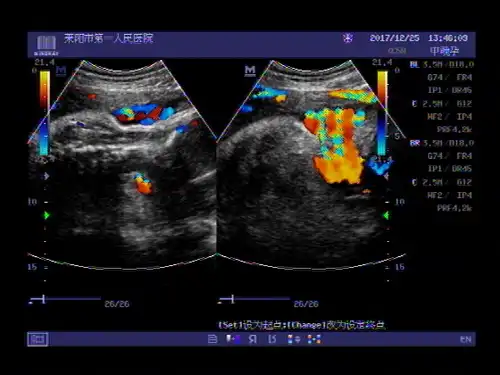

超声入门贴664---晚孕脐带绕颈三周